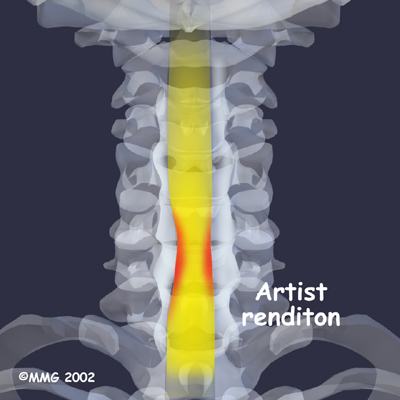

The bony spinal canal normally has more than enough room for the spinal cord. Typically, the canal is 17 to 18 millimeters around, slightly less than the size of a penny. Spinal stenosis occurs when the canal narrows to 13 millimeters or less. When the size drops to 10 millimeters, severe symptoms of myelopathy occur. Myelopathy is a term for any condition that affects the spinal cord. The symptoms of myelopathy result from pressure against the spinal cord and reduced blood supply in the spinal cord as a result of the pressure.

The changes that happen with degeneration and disc herniation can choke off the blood supply that goes to the spinal cord. The sections of the spinal cord that don't get blood have less oxygen and don't function normally, leading to symptoms of myelopathy.

X-rays are used to look for the cause of pressure against the spinal cord. The images can show if degeneration has caused the space between the vertebrae to collapse and may show if a bone spur is pressing against the spinal cord.

Collapsed Vertebrae